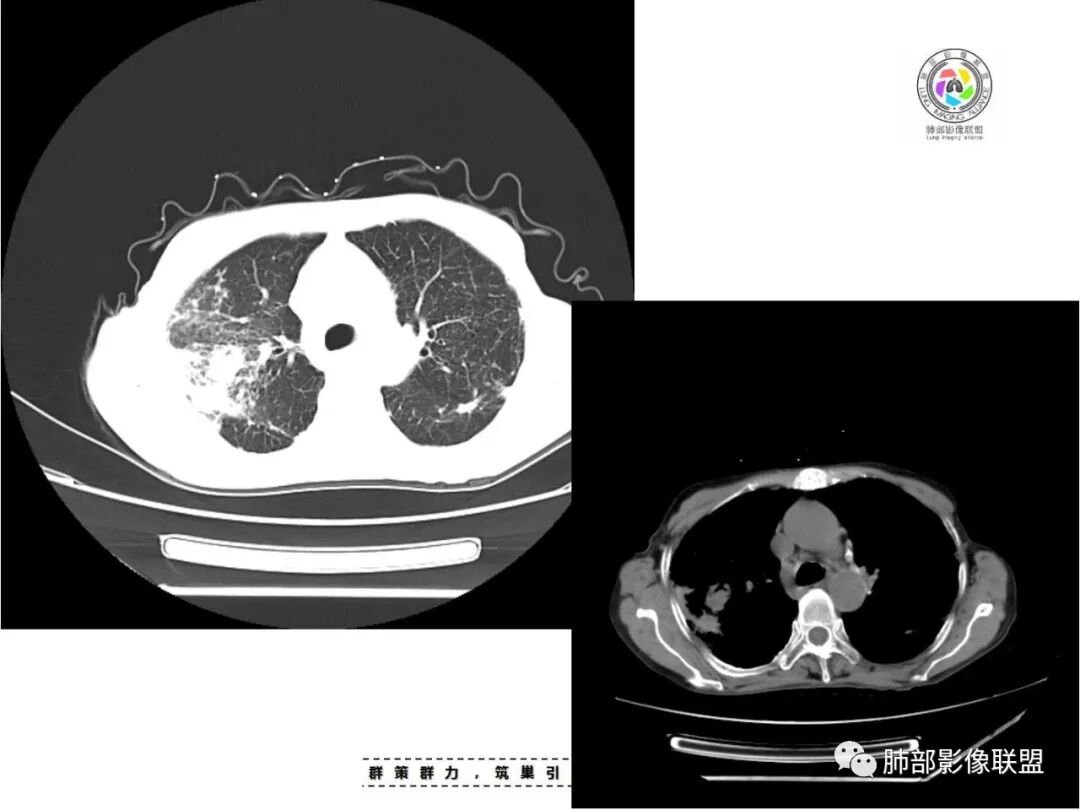

双上肺多发片状、索条影及小结节影,并见少许钙化,右肺上叶后段肿块,后段支气管阻塞,边缘膨隆,双上肺小叶间隔增厚呈多发结节状,胸膜局限性增厚,考虑:1、双肺上叶结核;2、右肺上叶后段腺癌并癌淋。

双肺多发斑片,索条及结节影,内可见钙化,右肺上叶后段支气管截断,断端圆钝略扩张,双肺门及纵膈淋巴结钙化,双侧胸膜增厚伴钙化。首先考虑结核。右肺上叶亚段气管分叉处结节,警惕肿瘤

老年女性,双肺索条纤维影,右肺上叶散在卫星灶,树芽征,小叶中心融合,右肺后段支气管圆形截断,实变病灶内支气管扩张,考虑结核。

患者老年女性,亚急性起病,主要症状表现为咳嗽、咳痰半月余,查体:双现呼吸音粗,双肺可闻及痰鸣音。胸部CT:双上肺胸膜下可见多发小叶实变影,双上肺可见多发小叶中心性结节及小叶间隔增厚,右上肺后段可见亚段性实变影,内见多发空洞,前段可见GGO及树芽征,后段局部支气管闭塞,肺门淋巴结肿大并钙化。病灶整体:有气道、间质播散,一元论考虑肺结核合并支气管结核可能性大,建议好好查痰;这样病灶:明显实变+空洞+气道播散,若是结核,痰涂片找到抗酸杆菌应该没问题。建议支气管镜检查助诊,了解有无支气管结核及合并腺癌的可能。

1.双肺片状影、大小不等斑片影、结节影、树芽等,病灶密度偏高多钙化。

2.病灶上肺为主,胸膜下分布为主。双肺病灶明显不对称,右肺块状影较大。

3.纤维条索影广泛杂乱、牵拉,横向分布为主,这点给人也印象很深!

1.本例结核诊断当无异议!

2.能够完全将尘肺排除在外吗(如II期)?不能!左肺内中带较均匀分布的较均匀是具有尘肺影像学特征而不支持结核血播的。此外双肺门及纵隔淋巴结钙化也更多见于尘肺,尤其是矽肺。

3.临床实践中,尘肺继发结核,有时如影随形!

如在原有尘肺病灶较短期内发生变化且病灶边界相对模糊时;原有尘肺基础上出现斑片影、树芽征,尤其是胸膜下呈簇状分布、不对称分布时;出现空洞性病灶时。